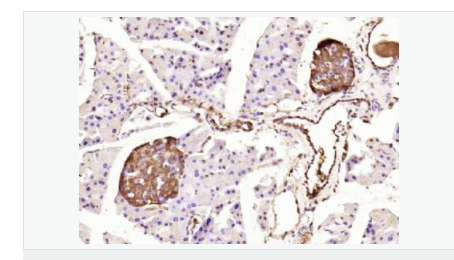

交叉反應(yīng):Human,Mouse,Rat(predicted:Dog,Pig,Cow,Rabbit,Sheep,GuineaPig) 推薦應(yīng)用:IHC-P,IHC-F,ICC,IF,Flow-Cyt,ELISA

| 產(chǎn)品應(yīng)用 | ELISA=1:5000-10000 IHC-P=1:100-500 IHC-F=1:100-500 Flow-Cyt=1ug/Test ICC=1:100-500 IF=1:100-500 (石蠟切片需做抗原修復(fù)) not yet tested in other applications. optimal dilutions/concentrations should be determined by the end user. |

| 產(chǎn)品介紹 | Insulin receptor substrates (IRS) are responsible for several insulin related activities, such as glucose homeostasis, cell growth, cell transformation, apoptosis and insulin signal transduction. Serine/threonine phosphorylation of IRS1 has been demonstrated to be a negative regulator of insulin signaling and is responsible for its degradation, although IRS1 degradation pathways are not well understood. IRS1 has also been shown to be constitutively activated in cancers such as breast cancer, Wilm's tumors, and adrenal cortical carcinomas, thus making IRS1 phosphorylation and subsequent degradation an attractive therapeutic target. To date there have been four subtypes identified: IRS1, 2, 3 and 4, with IRS1 being widely expressed. Function: May mediate the control of various cellular processes by insulin. When phosphorylated by the insulin receptor binds specifically to various cellular proteins containing SH2 domains such as phosphatidylinositol 3-kinase p85 subunit or GRB2. Activates phosphatidylinositol 3-kinase when bound to the regulatory p85 subunit. Subunit: Interacts with UBTF and PIK3CA (By similarity). Interacts (via phosphorylated YXXM motifs) with PIK3R1 (By similarity). Interacts with ROCK1 and FER (By similarity). Interacts (via PH domain) with PHIP (By similarity). Interacts with GRB2 (By similarity). Interacts with SOCS7. Interacts (via IRS-type PTB domain) with IGF1R and INSR (via the tyrosine-phosphorylated NPXY motif). Interacts with ALK. Interacts with EIF2AK2/PKR (By similarity). Subcellular Location: Membrane; Single-pass type I membrane protein. Tissue Specificity: Isoform Long and isoform Short are predominantly expressed in tissue targets of insulin metabolic effects: liver, adipose tissue and skeletal muscle but are also expressed in the peripheral nerve, kidney, pulmonary alveoli, pancreatic acini, placenta vascular endothelium, fibroblasts, monocytes, granulocytes, erythrocytes and skin. Isoform Short is preferentially expressed in fetal cells such as fetal fibroblasts, muscle, liver and kidney. Found as a hybrid receptor with IGF1R in muscle, heart, kidney, adipose tissue, skeletal muscle, hepatoma, fibroblasts, spleen and placenta (at protein level). Overexpressed in several tumors, including breast, colon, lung, ovary, and thyroid carcinomas. Post-translational modifications: Serine phosphorylation of IRS1 is a mechanism for insulin resistance. Ser-312 phosphorylation inhibits insulin action through disruption of IRS1 interaction with the insulin receptor (By similarity). Phosphorylation of Tyr-896 is required for GRB2-binding (By similarity). Phosphorylated by ALK. Phosphorylated at Ser-270, Ser-307, Ser-636 and Ser-1101 by RPS6KB1; phosphorylation induces accelerated degradation of IRS1. DISEASE: Polymorphisms in IRS1 may be involved in the etiology of non-insulin-dependent diabetes mellitus (NIDDM) [MIM:125853]. Similarity: Contains 1 IRS-type PTB domain. Contains 1 PH domain. SWISS: P35568 Gene ID: 3667 Database links: Entrez Gene: 3667 Human Omim: 147545 Human SwissProt: P35568 Human Unigene: 471508 Human Important Note: This product as supplied is intended for research use only, not for use in human, therapeutic or diagnostic applications. |